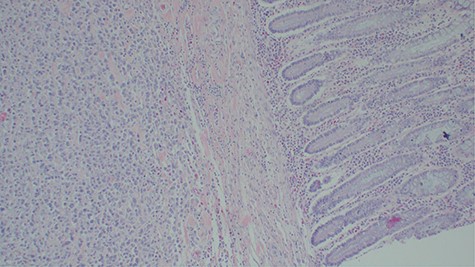

Laboratory investigations revealed a low platelet level of 53 per microliter and hemoglobin level of 10.7 g/dl. Renal profile, white blood count and serum electrolytes were within normal range. Computed tomography intravenous urogram revealed a large heterogeneous mass, measuring 5.5 × 4.5 cm at the right superolateral aspect of the urinary bladder with ipsilateral hydronephrosis and hydroureter. Bone scan study was unremarkable. Urothelial cell carcinoma of the urinary bladder was clinically suggested as the most likely differential diagnosis. Cystoscopy was done under spinal anesthesia, which revealed a solid mass with areas of necrosis at the anterior bladder wall. The biopsy was taken whose histological evaluation revealed a high-grade malignant mesenchymal tumor made up of oval or spindle cells with osteoid formation in many areas of the lesion (Fig. 1). No definite carcinomatous component was appreciated. The tumor was strongly positive for vimentin immunohistochemistry staining (Fig. 2) and negative for cytokeratin 20. Calcified schistosomal ova were also seen (Fig. 3).

Histopathology of urinary bladder tumor showing oval- to spindle-shaped cells with abundant osteoid matrix deposition (H&E stain, ×200).

Histopathology of the urinary bladder osteosarcoma metastasizing into the colon. Adjacent normal colon mucosa is seen near the tumor (H&E ×200).